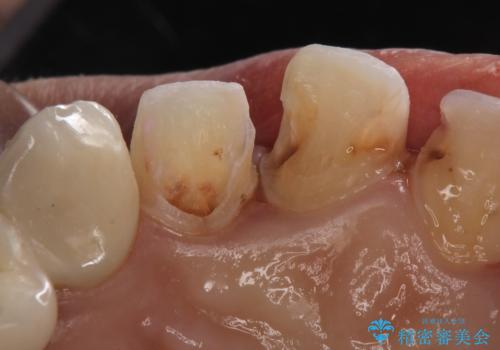

- 保険治療のプラスチックでつぎはぎの歯をセラミックにし、一緒に前歯の並びもきれいにしたいとのご希望でした。

特に裏側のつぎはぎ、二次う蝕(治したところの境目からの虫歯)が多く、審美目的だけでなく、虫歯の治療としても意味があったと思います。

神経を温存するようにあまり削らないように治療しました。